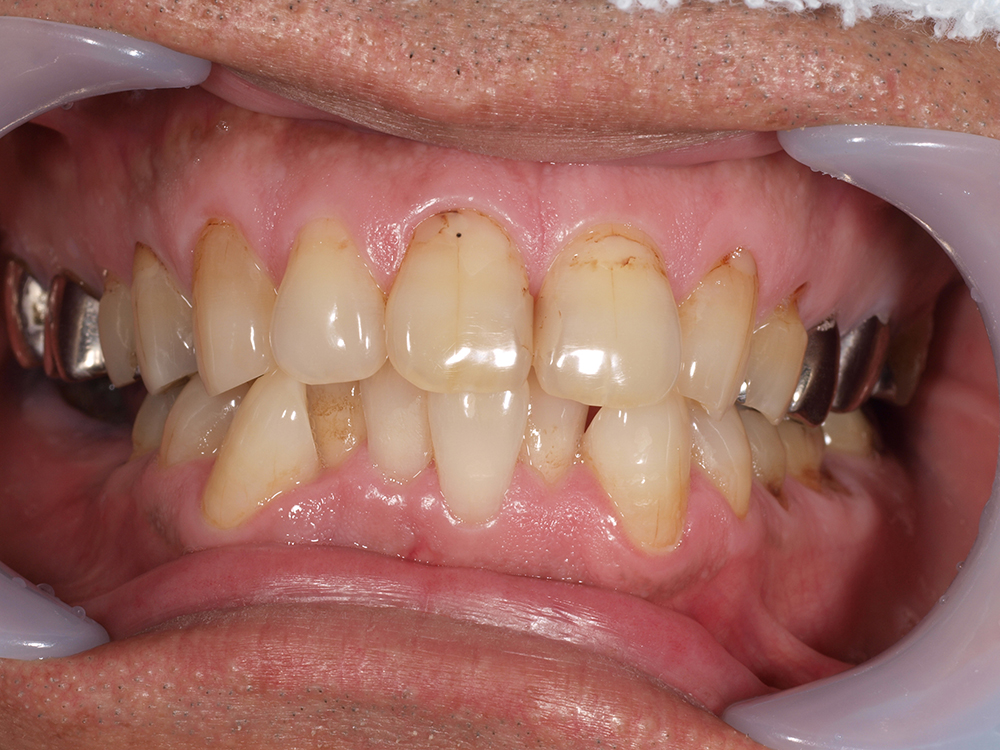

53歳 男性

- 主訴

- 全然噛めない。上の歯が取れてきた

- 処置内容

- 上顎:8本 下顎:2本

- 治療費用

- 上顎:約320万円(税込)、下顎:約160万円(税込)

- 治療期間

-

上顎:1年(仮歯まで8か月)

下顎:8か月(仮歯まで5か月)

- リスク

- 上部構造物、仮歯の破折、術後の腫れ(3日)、人工歯根脱落リスクがあります